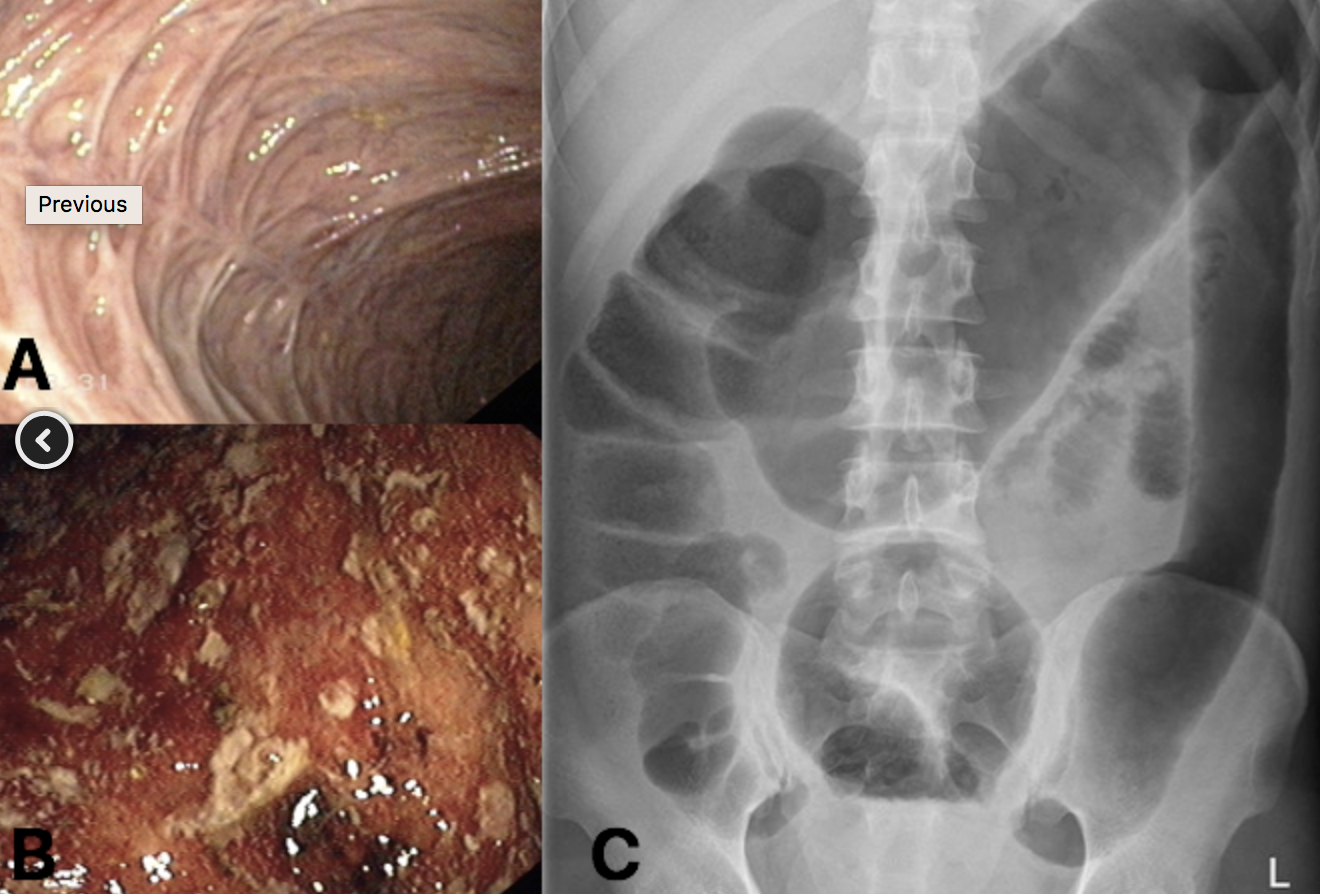

Erythema nodosum – tender red/purple subcutaneous nodules, typically found on the patient’s shins (Fig. 2A)

Pyoderma gangrenosum – erythematous papules/pustules that develop into deep ulcers (Fig. 2B) and can occur anywhere (yet typically affect the shins)

(A) bowel fibrosis, secondary to chronic UC (B) active inflammation in patient with UC (C) AXR changes in active UC, showing toxic megacolon with lead-pipe colon (seen in descending colon)